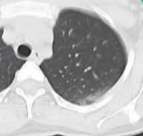

监测 血氧饱和度 SpO2 96%: SpO(血氧饱和度) 是评估身体是否获得足够氧气的第五大生命体征(另外四个是体温、脉搏、呼吸和血压) Hb 12.8 PLT 12.8 CREAT 0.9 考虑 年轻 无共病情况 没有抗凝治疗 左侧先天性单肾

监测

血氧饱和度 SpO2 96%:

SpO₂(血氧饱和度) 是评估身体是否获得足够氧气的第五大生命体征(另外四个是体温、脉搏、呼吸和血压)